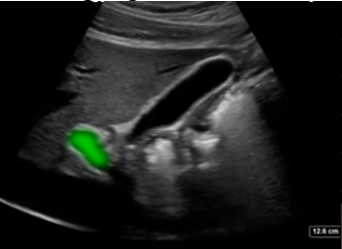

Gallbladder Portal Vein Image

Highlighted Area: Portal Vein (PV)